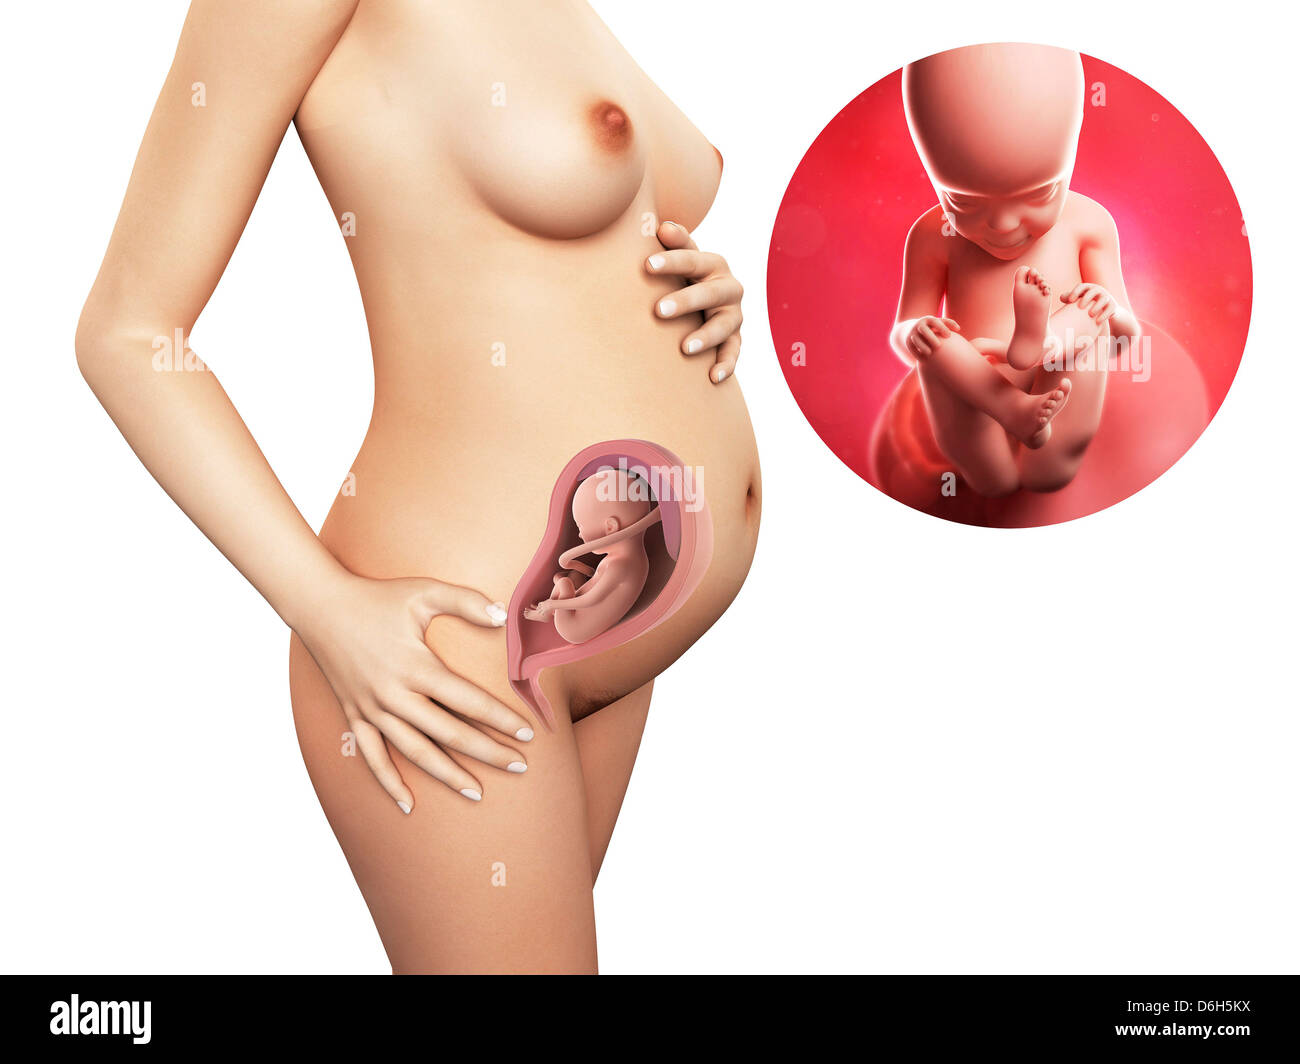

Feto a 27 settimane, artwork Foto Stockhttps://www.alamy.it/image-license-details/?v=1https://www.alamy.it/foto-immagine-feto-a-27-settimane-artwork-52731084.html

Feto a 27 settimane, artwork Foto Stockhttps://www.alamy.it/image-license-details/?v=1https://www.alamy.it/foto-immagine-feto-a-27-settimane-artwork-52731084.htmlRFD1P310–Feto a 27 settimane, artwork

Feto umano età 27 settimane, illustrazione. Foto Stockhttps://www.alamy.it/image-license-details/?v=1https://www.alamy.it/foto-immagine-feto-umano-eta-27-settimane-illustrazione-147221626.html

Feto umano età 27 settimane, illustrazione. Foto Stockhttps://www.alamy.it/image-license-details/?v=1https://www.alamy.it/foto-immagine-feto-umano-eta-27-settimane-illustrazione-147221626.htmlRFJFEEK6–Feto umano età 27 settimane, illustrazione.

Feto umano età 27 settimane, illustrazione. Foto Stockhttps://www.alamy.it/image-license-details/?v=1https://www.alamy.it/foto-immagine-feto-umano-eta-27-settimane-illustrazione-118698396.html

Feto umano età 27 settimane, illustrazione. Foto Stockhttps://www.alamy.it/image-license-details/?v=1https://www.alamy.it/foto-immagine-feto-umano-eta-27-settimane-illustrazione-118698396.htmlRFGW350C–Feto umano età 27 settimane, illustrazione.

Feto umano età 27 settimane, illustrazione. Foto Stockhttps://www.alamy.it/image-license-details/?v=1https://www.alamy.it/foto-immagine-feto-umano-eta-27-settimane-illustrazione-112681659.html

Feto umano età 27 settimane, illustrazione. Foto Stockhttps://www.alamy.it/image-license-details/?v=1https://www.alamy.it/foto-immagine-feto-umano-eta-27-settimane-illustrazione-112681659.htmlRFGF92GY–Feto umano età 27 settimane, illustrazione.

Feto umano età 27 settimane, illustrazione. Foto Stockhttps://www.alamy.it/image-license-details/?v=1https://www.alamy.it/foto-immagine-feto-umano-eta-27-settimane-illustrazione-111973828.html

Feto umano età 27 settimane, illustrazione. Foto Stockhttps://www.alamy.it/image-license-details/?v=1https://www.alamy.it/foto-immagine-feto-umano-eta-27-settimane-illustrazione-111973828.htmlRFGE4RN8–Feto umano età 27 settimane, illustrazione.

Gravidanza - settimana 27, illustrazione Foto Stockhttps://www.alamy.it/image-license-details/?v=1https://www.alamy.it/foto-immagine-gravidanza-settimana-27-illustrazione-55696702.html

Gravidanza - settimana 27, illustrazione Foto Stockhttps://www.alamy.it/image-license-details/?v=1https://www.alamy.it/foto-immagine-gravidanza-settimana-27-illustrazione-55696702.htmlRFD6H5KX–Gravidanza - settimana 27, illustrazione

Feto umano alla settimana 27, illustrazione Foto Stockhttps://www.alamy.it/image-license-details/?v=1https://www.alamy.it/feto-umano-alla-settimana-27-illustrazione-image463765768.html

Feto umano alla settimana 27, illustrazione Foto Stockhttps://www.alamy.it/image-license-details/?v=1https://www.alamy.it/feto-umano-alla-settimana-27-illustrazione-image463765768.htmlRF2HXE9Y4–Feto umano alla settimana 27, illustrazione

Feto umano alla settimana 27, illustrazione Foto Stockhttps://www.alamy.it/image-license-details/?v=1https://www.alamy.it/feto-umano-alla-settimana-27-illustrazione-image463765769.html

Feto umano alla settimana 27, illustrazione Foto Stockhttps://www.alamy.it/image-license-details/?v=1https://www.alamy.it/feto-umano-alla-settimana-27-illustrazione-image463765769.htmlRF2HXE9Y5–Feto umano alla settimana 27, illustrazione

Feto umano alla settimana 27, illustrazione Foto Stockhttps://www.alamy.it/image-license-details/?v=1https://www.alamy.it/feto-umano-alla-settimana-27-illustrazione-image463765837.html

Feto umano alla settimana 27, illustrazione Foto Stockhttps://www.alamy.it/image-license-details/?v=1https://www.alamy.it/feto-umano-alla-settimana-27-illustrazione-image463765837.htmlRF2HXEA1H–Feto umano alla settimana 27, illustrazione

Feto umano alla settimana 27, illustrazione Foto Stockhttps://www.alamy.it/image-license-details/?v=1https://www.alamy.it/feto-umano-alla-settimana-27-illustrazione-image463765857.html

Feto umano alla settimana 27, illustrazione Foto Stockhttps://www.alamy.it/image-license-details/?v=1https://www.alamy.it/feto-umano-alla-settimana-27-illustrazione-image463765857.htmlRF2HXEA29–Feto umano alla settimana 27, illustrazione

Feto umano alla settimana 27, illustrazione Foto Stockhttps://www.alamy.it/image-license-details/?v=1https://www.alamy.it/feto-umano-alla-settimana-27-illustrazione-image463765740.html

Feto umano alla settimana 27, illustrazione Foto Stockhttps://www.alamy.it/image-license-details/?v=1https://www.alamy.it/feto-umano-alla-settimana-27-illustrazione-image463765740.htmlRF2HXE9X4–Feto umano alla settimana 27, illustrazione

Anatomia del feto umano alla settimana 27, illustrazione Foto Stockhttps://www.alamy.it/image-license-details/?v=1https://www.alamy.it/anatomia-del-feto-umano-alla-settimana-27-illustrazione-image463765847.html

Anatomia del feto umano alla settimana 27, illustrazione Foto Stockhttps://www.alamy.it/image-license-details/?v=1https://www.alamy.it/anatomia-del-feto-umano-alla-settimana-27-illustrazione-image463765847.htmlRF2HXEA1Y–Anatomia del feto umano alla settimana 27, illustrazione

Anatomia del feto umano alla settimana 27, illustrazione Foto Stockhttps://www.alamy.it/image-license-details/?v=1https://www.alamy.it/anatomia-del-feto-umano-alla-settimana-27-illustrazione-image463765833.html

Anatomia del feto umano alla settimana 27, illustrazione Foto Stockhttps://www.alamy.it/image-license-details/?v=1https://www.alamy.it/anatomia-del-feto-umano-alla-settimana-27-illustrazione-image463765833.htmlRF2HXEA1D–Anatomia del feto umano alla settimana 27, illustrazione

Anatomia del feto umano alla settimana 27, illustrazione Foto Stockhttps://www.alamy.it/image-license-details/?v=1https://www.alamy.it/anatomia-del-feto-umano-alla-settimana-27-illustrazione-image463765820.html

Anatomia del feto umano alla settimana 27, illustrazione Foto Stockhttps://www.alamy.it/image-license-details/?v=1https://www.alamy.it/anatomia-del-feto-umano-alla-settimana-27-illustrazione-image463765820.htmlRF2HXEA10–Anatomia del feto umano alla settimana 27, illustrazione

Anatomia del feto umano alla settimana 27, illustrazione Foto Stockhttps://www.alamy.it/image-license-details/?v=1https://www.alamy.it/anatomia-del-feto-umano-alla-settimana-27-illustrazione-image463765855.html

Anatomia del feto umano alla settimana 27, illustrazione Foto Stockhttps://www.alamy.it/image-license-details/?v=1https://www.alamy.it/anatomia-del-feto-umano-alla-settimana-27-illustrazione-image463765855.htmlRF2HXEA27–Anatomia del feto umano alla settimana 27, illustrazione

Anatomia del feto umano alla settimana 27, illustrazione Foto Stockhttps://www.alamy.it/image-license-details/?v=1https://www.alamy.it/anatomia-del-feto-umano-alla-settimana-27-illustrazione-image463765763.html

Anatomia del feto umano alla settimana 27, illustrazione Foto Stockhttps://www.alamy.it/image-license-details/?v=1https://www.alamy.it/anatomia-del-feto-umano-alla-settimana-27-illustrazione-image463765763.htmlRF2HXE9XY–Anatomia del feto umano alla settimana 27, illustrazione